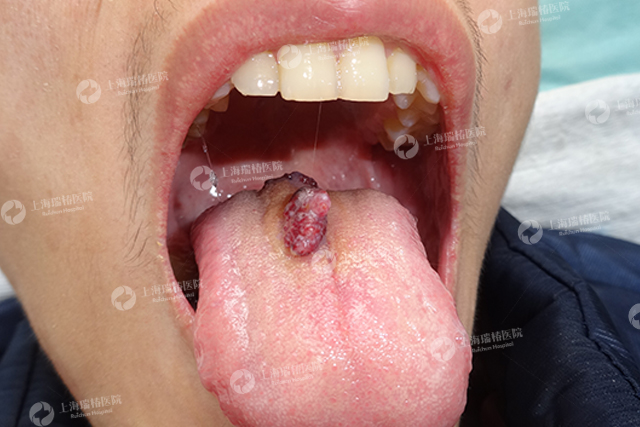

梁绍洪-草莓状-28岁-舌部-中度